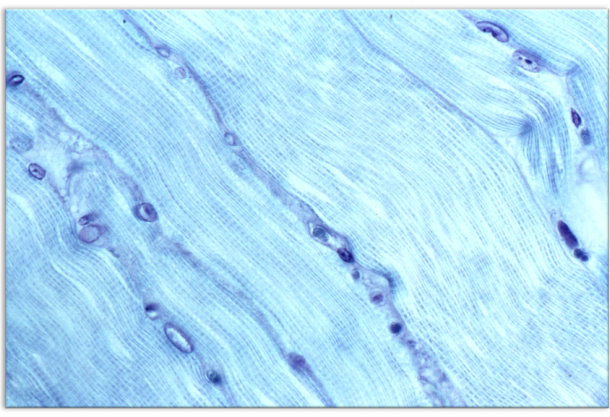

2. Using LR Gold